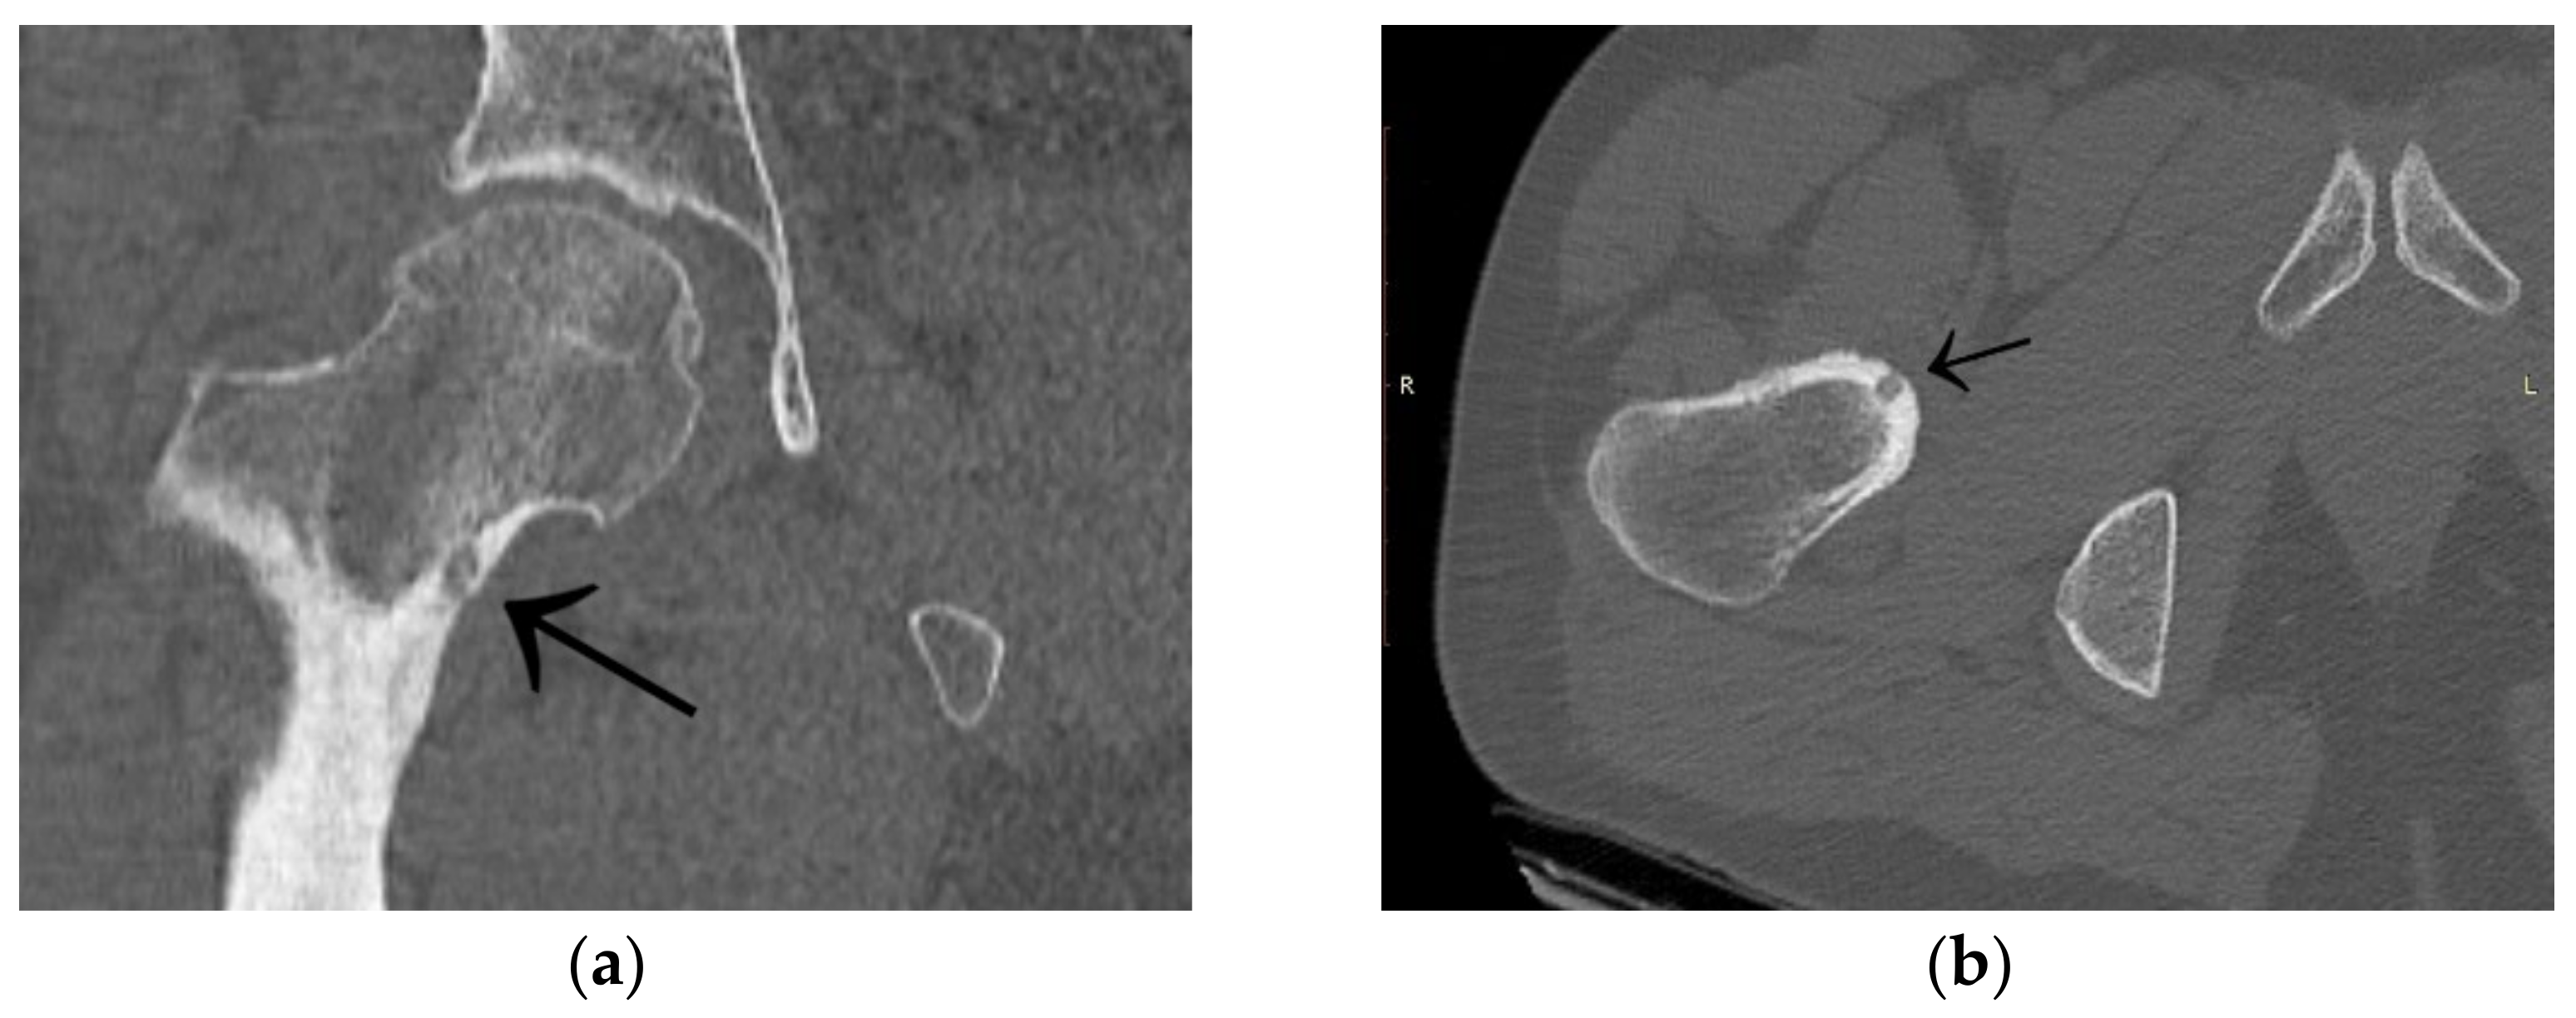

3.1. Case 1: OO Masking as Femoroacetabular Impingement (FAI)

3.4. Case 4: OO Masking as a Fatigue Fracture